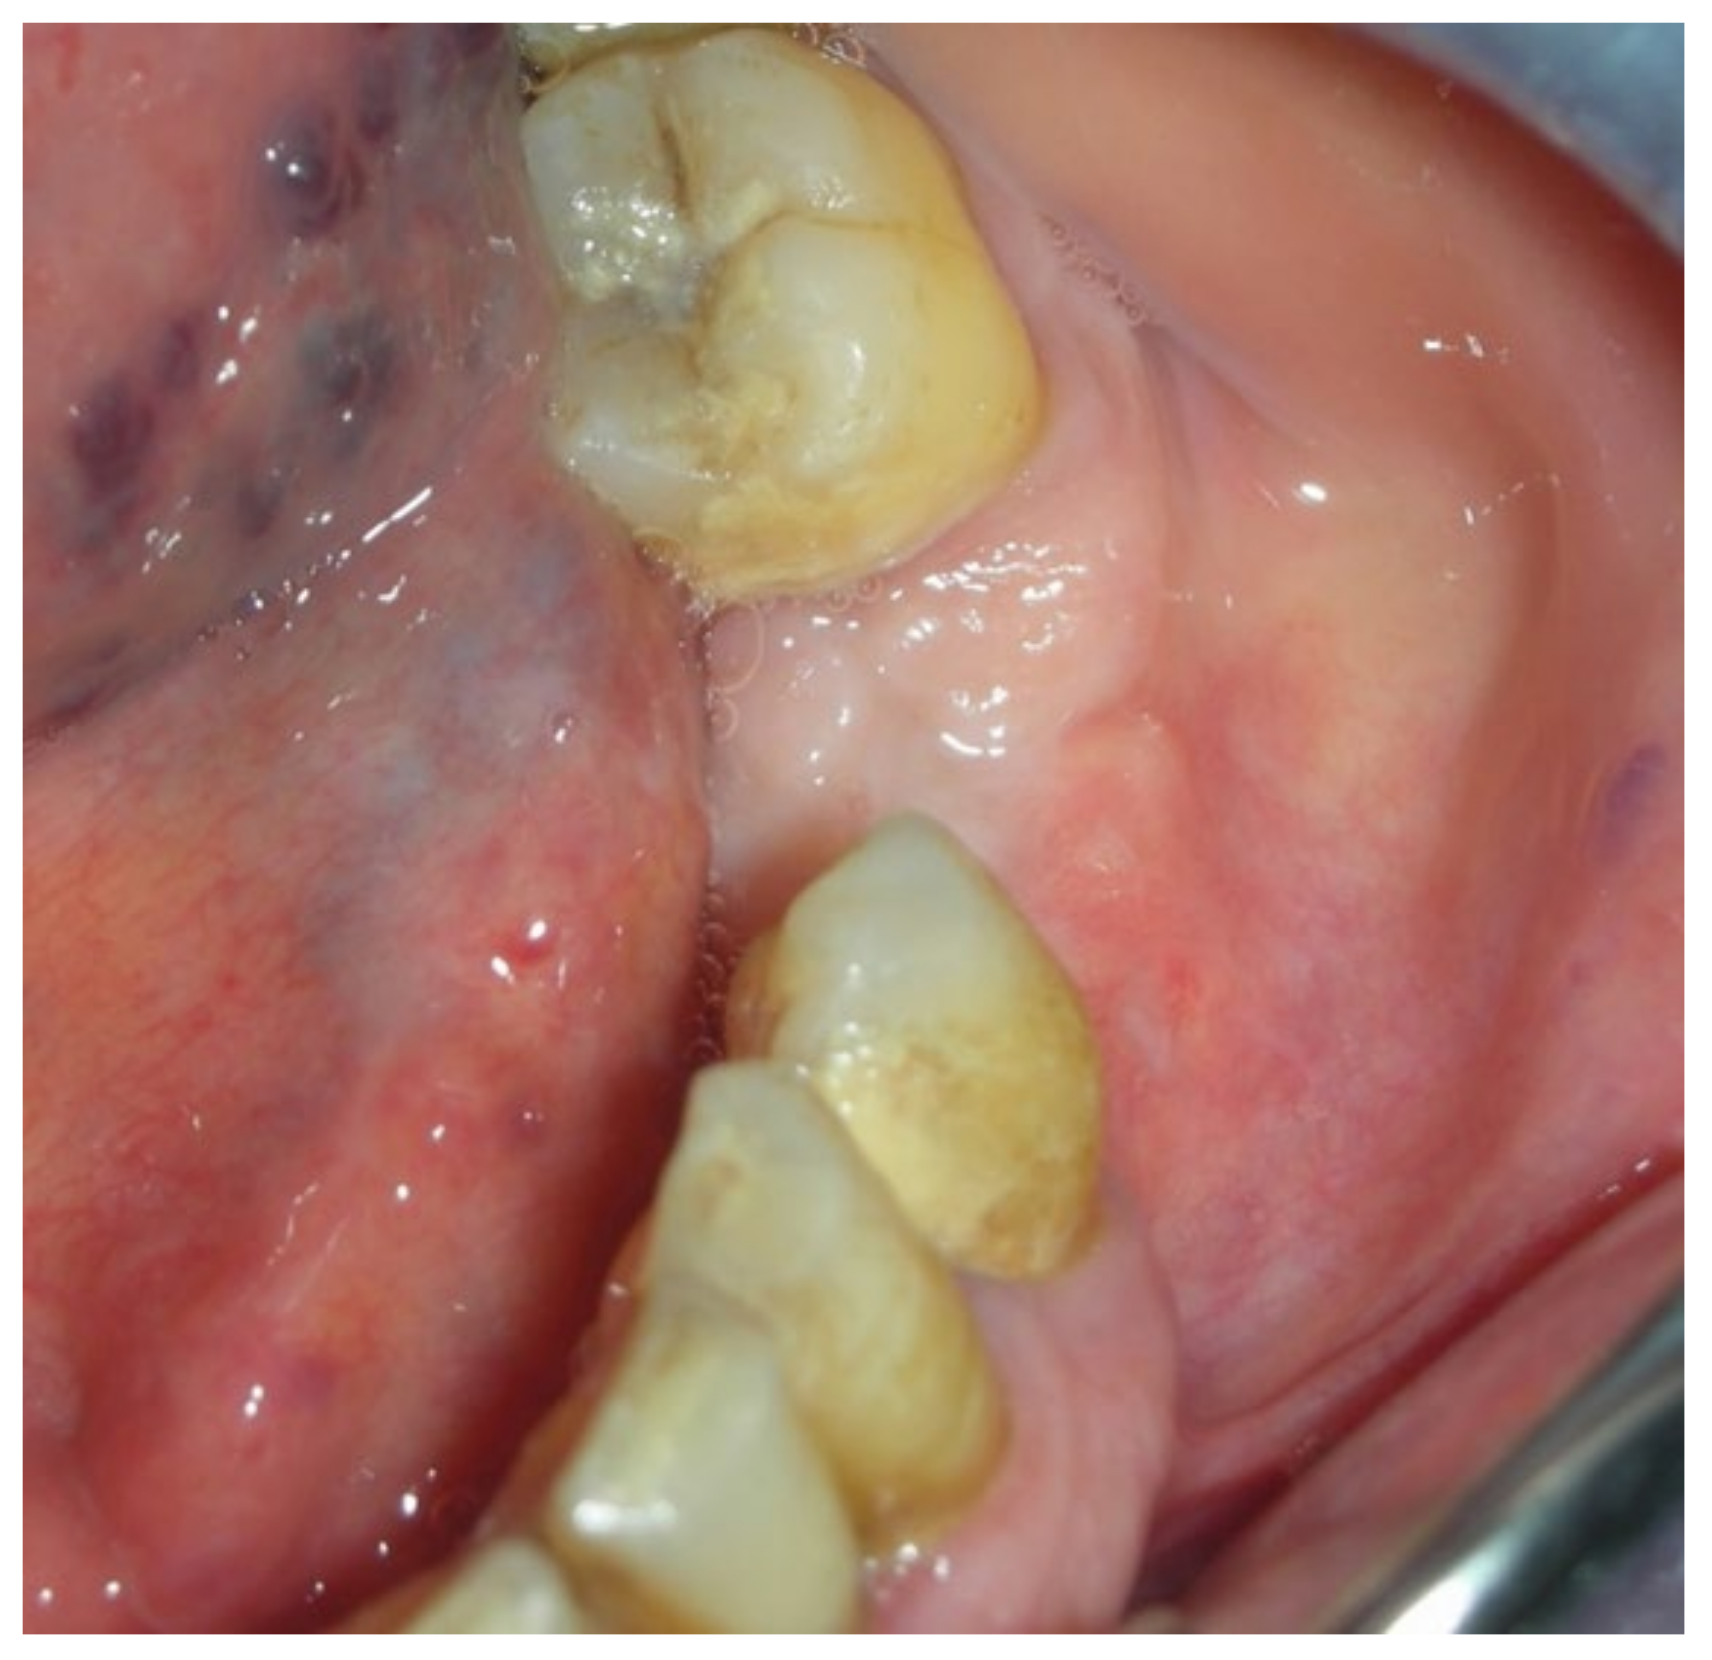

3.3. Clinical Case 3

3.4. Clinical Case 4